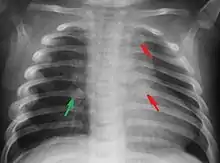

Most nations with child abuse laws deem the deliberate infliction of serious injuries, or actions that place the child at obvious risk of serious injury or death, to be illegal.[36] Bruises, scratches, burns, broken bones, lacerations—as well as repeated "mishaps", and rough treatment that could cause physical injuries—can be physical abuse.[37] Multiple injuries or fractures at different stages of healing can raise suspicion of abuse.

C. Henry Kempe and his colleagues were the first to describe the battered-child syndrome in 1962.[40] The battered-child syndrome is a term used to describe a collection of injuries that young children sustain as a result of repeated physical abuse or neglect.[41][42] These symptoms may include: fractures of bones, multiple soft tissue injuries, subdural hematoma (bleeding in the brain), malnutrition, and poor skin hygiene.[42][43]

The immediate physical effects of abuse or neglect can be relatively minor (bruises or cuts) or severe (broken bones, hemorrhage, death). Certain injuries, such as rib fractures or femoral fractures in infants that are not yet walking, may increase suspicion of child physical abuse, although such injuries are only seen in a fraction of children suffering physical abuse.[92][93] Cigarette burns or scald injuries may also prompt evaluation for child physical abuse.[94]

Suspicion for physical abuse is recommended when injuries occur in a child who is not yet able to walk independently.[173] Additionally, having multiple injuries that are in different stages of healing and having injuries in unusual location, such as the torso, ears, face, or neck, may prompt evaluation for child abuse.[173] Medical professionals may also become suspicious of child abuse when a caregiver is not able to provide an explanation for an injury that is consistent with the type or severity of the injury.[174]